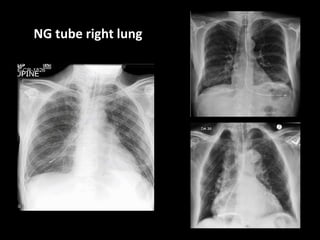

NG tube right lung

Left lower lobe posterior segment consolidation